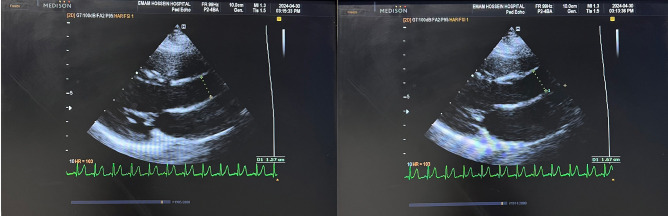

Methods: This study aimed to investigate the cardiovascular health of children with MIS-C compared to healthy controls. Fifty-nine children with MIS-C and fifty-nine healthy individuals were included in this cohort study. Non-invasive techniques were employed to measure the brachial artery's flow-mediated dilation (FMD), aortic distensibility (AD), and aortic strain (AS).

Abstract Image